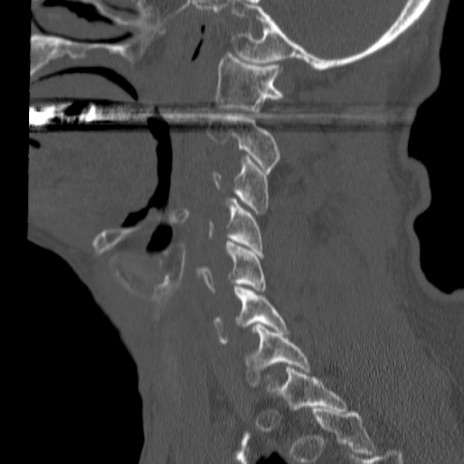

症例46 頚椎CT(矢状断像)

【症例】80歳代男性

【主訴】両側頚部〜上肢のしびれ

【現病歴】昨日、自宅内で転倒、その後より上記症状あり。意識障害なし。

【身体所見】両側上肢のallodynia(熱痛覚過敏)あり。MMTおよびDTRは正確な所見取れず。両上肢の挙上はなんとか可能。

異常所見と診断は?